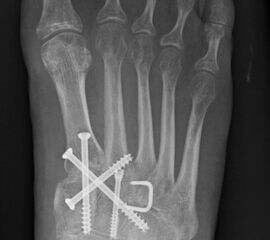

In der Regel werden die physiologisch rigiden TMT-1 bis 3 mittels Schrauben transfixiert. Hierfür werden meist kanülierte Kleinfragment-Kortikalisschrauben (3,5 oder 4 mm) verwendet. Diese können in Stellschraubentechnik von der Metatarsale-1-Basis in das Os cuneiforme mediale (Abb. 17) sowie vom Os cuneifome mediale in die Metatarsale-2-Basis und bei zusätzlicher intercuneiformer Instabilität vom Os cuneifome mediale in das Os cuneifome intermedium eingebracht werden.

Zum Lesen der Bildbeschreibung und zur Vollansicht bitte das Bild anklicken.

Ggf. wird zusätzlich ein K-Draht oder eine Schraube von der Metatarsale-2-Basis in das Os cuneiforme intermedium gebohrt (Abb. 18). Zur Transfixation der TMT-4 und 5-Gelenke werden, entsprechend ihres höheren physiologischen Bewegungsumfangs meist K-Drähte empfohlen. Die Indikation zur Transfixation wird von den meisten Autoren nur bei einer Instabilität gesehen, einige empfehlen eine Transfixation sämtlicher TMT-Gelenke unabhängig vom Ausmaß der Instabilität 10. Kleine, nicht refixierbare Fragmente sollten entfernt werden. Ist ein primärer Hautverschluss nicht möglich, erfolgt die temporäre Weichteildeckung mit Kunsthaut wie Epigard 112951710.